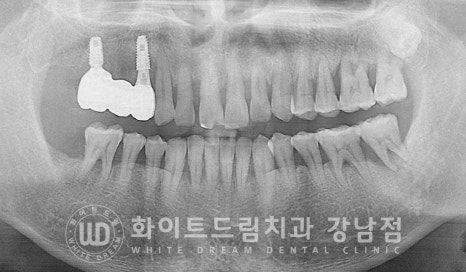

임플란트 식립 후 x-ray 사진입니다.

아직은 치아가 빠진 빈 공간, 발치와가 눈으로 확인이 됩니다.

이 발치와는 시간이 지나면서 잇몸뼈로 채워지게 되는데

임플란트 주위로 잇몸뼈가 두툼하게 잘 형성될 수 있도록

임플란트 식립 후 남은 빈 공간은 뼈이식재를 함께 넣고

봉합하면 큰 수술은 끝나게 됩니다.

24.04.29 수술